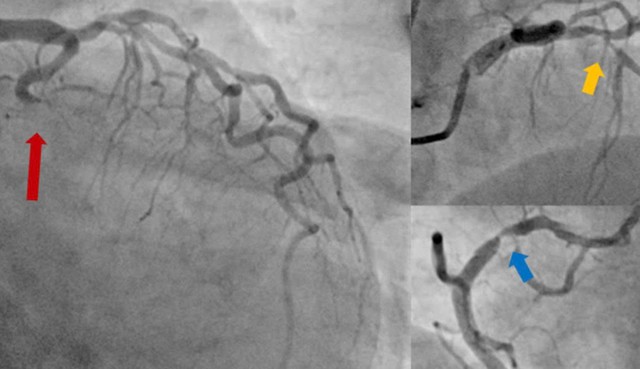

Hình ảnh mạch vành của người bệnh sau khi đã được can thiệp tái thông toàn bộ các động mạch vành tắc và hẹp.

Việc can thiệp tái thông hoàn toàn cả động mạch thủ phạm và hai động mạch hẹp nặng là phù hợp với các khuyến cáo hiện hành và sẽ giúp khả năng cứu được người bệnh cao hơn.

Sau khi giải thích kỹ chẩn đoán, định hướng điều trị, các lợi ích và nguy cơ của thủ thuật cho người nhà, bệnh nhân lần lượt được can thiệp nong bóng và đặt stent thành công cả ba nhánh động mạch mũ, động mạch liên thất trước và động mạch vành phải.